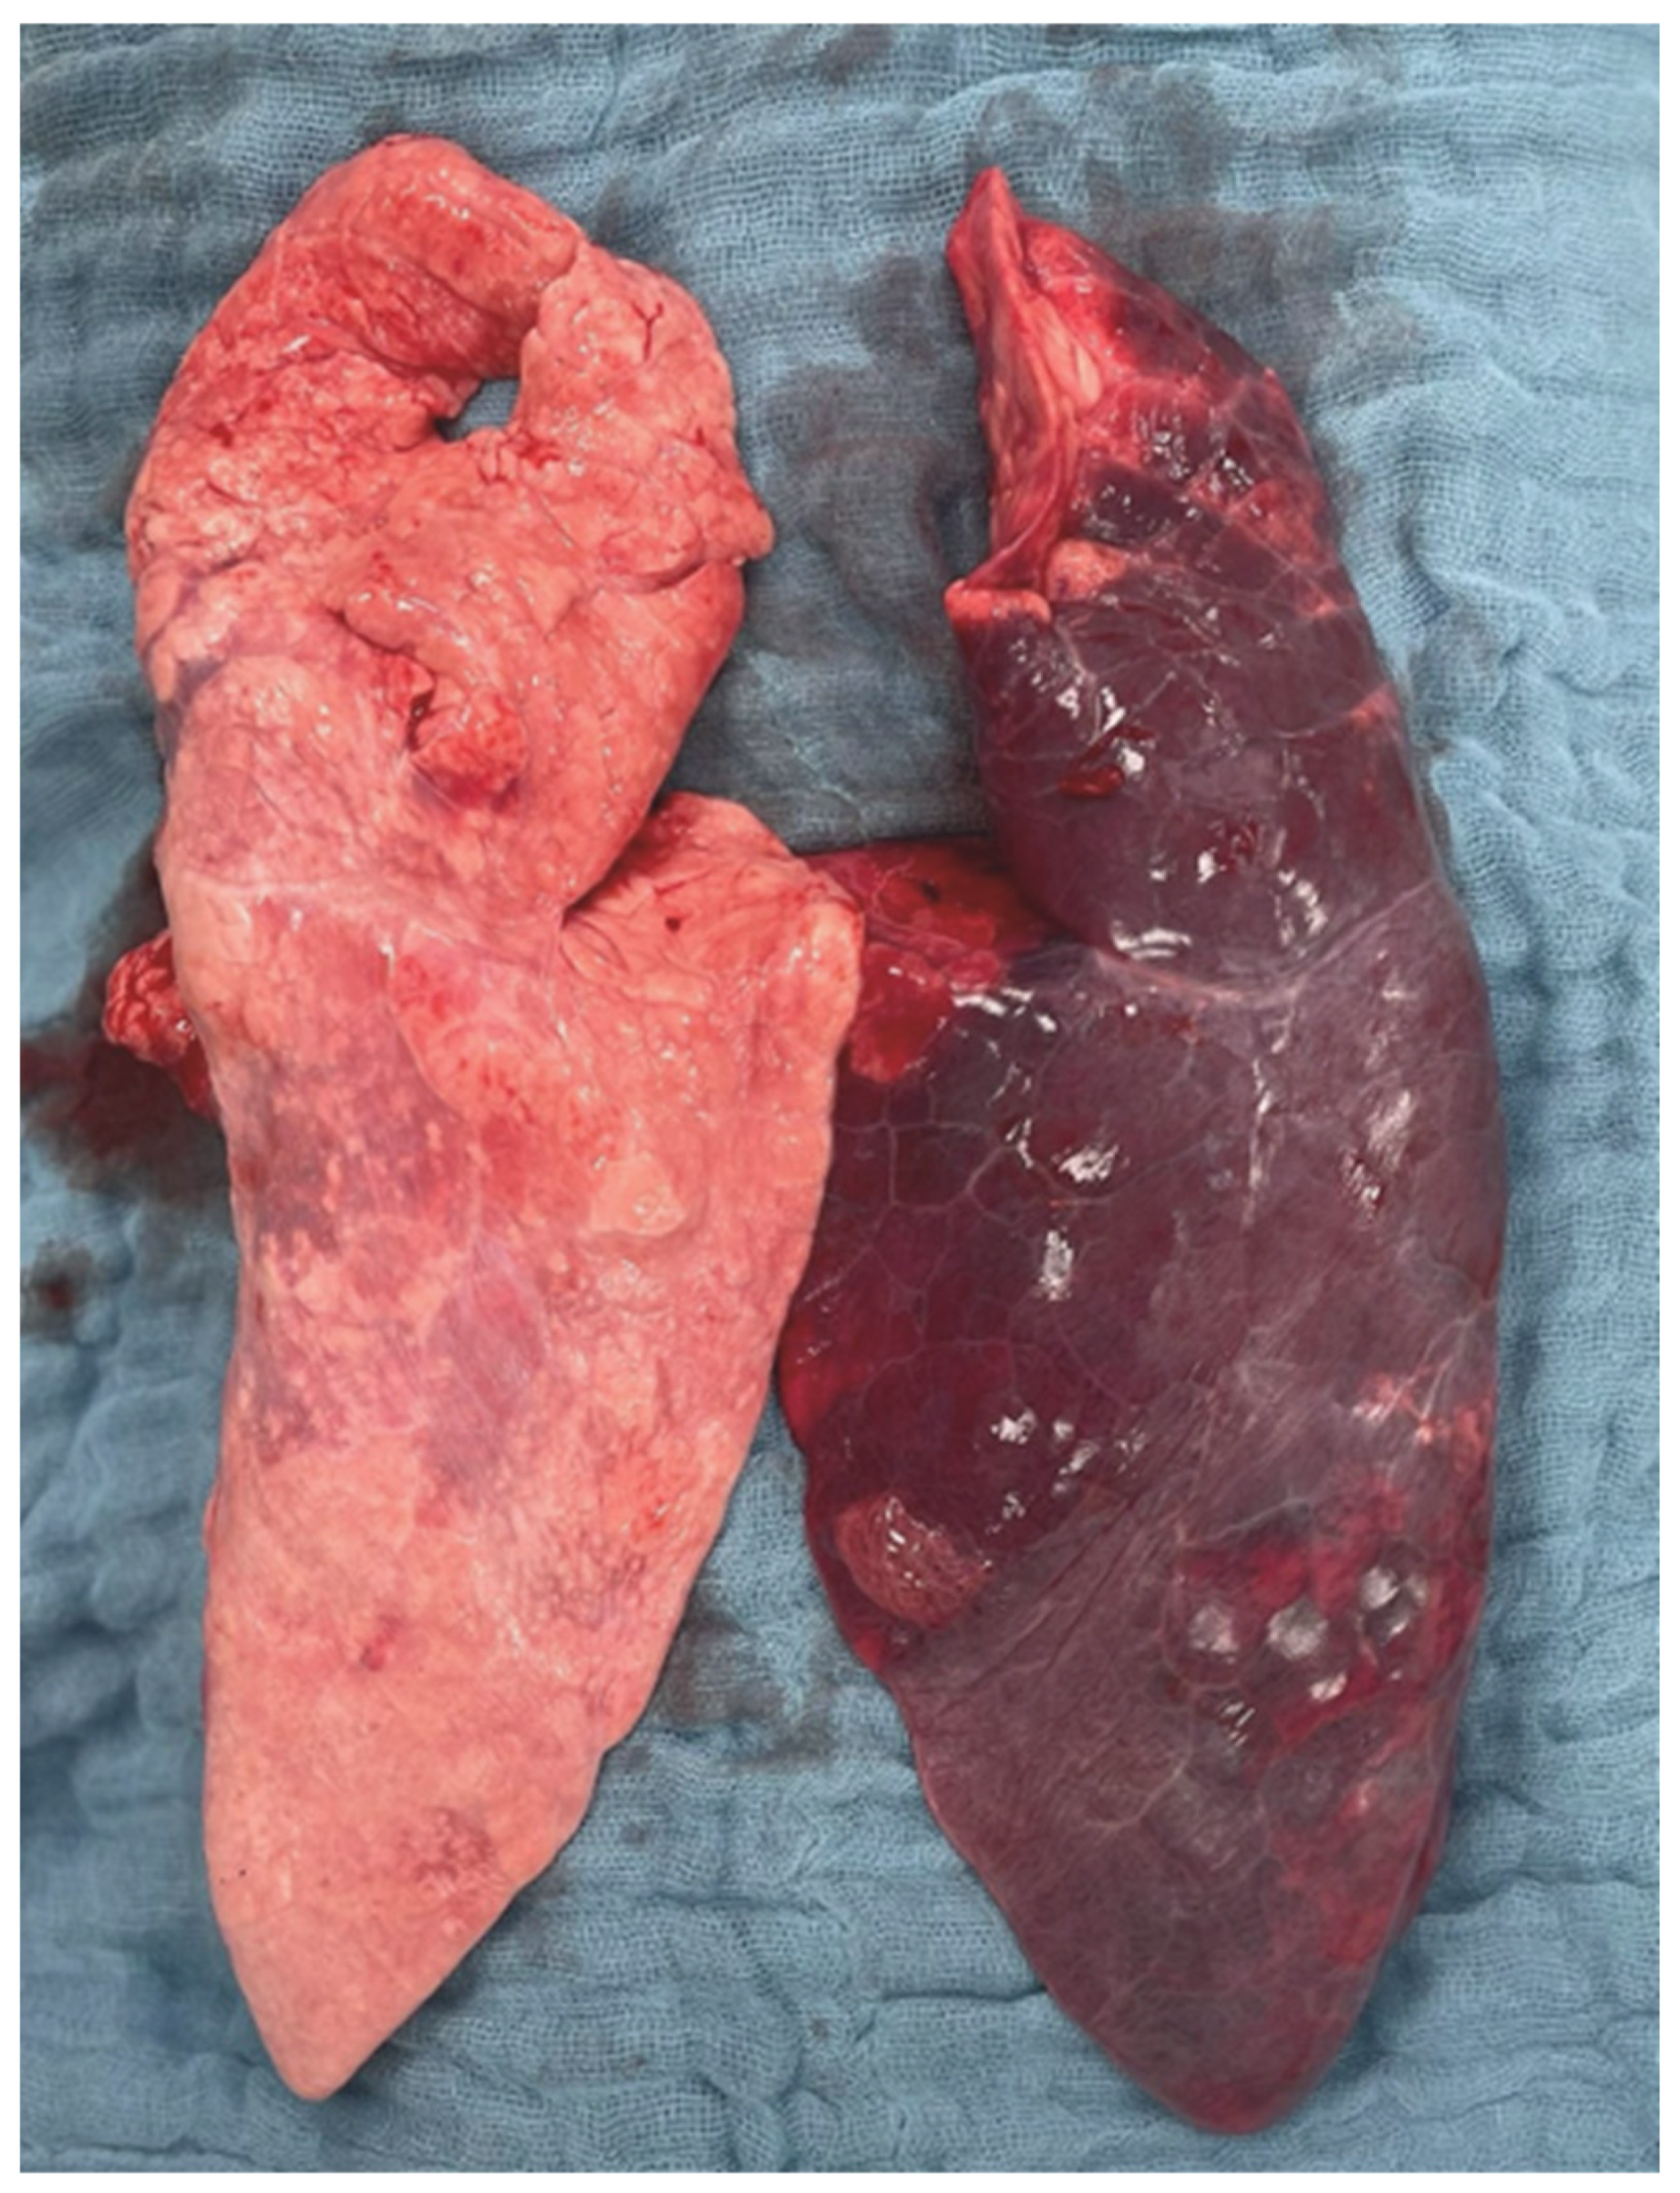

2.3. Histopathological Lung Injury Score

2.3.1. Left vs. Right Lung

2.3.2. Intergroup Differences

3.4. Histopathological Findings